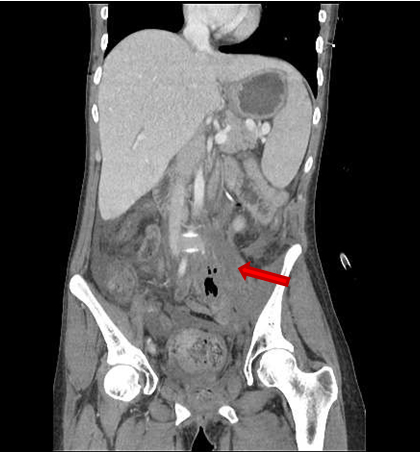

One month after surgery, late toxicity came up, with three consecutive radiation related fistulae (Figure 5), (Figure 6) and (Figure 7). Vesicovaginal and rectovaginal fistulae caused recurrent urinary tract and vaginal infections and abdominal pain, and required intravenous antibiotic therapy, nutritional replacement, and diversion colostomy. A further third fistula connecting the small intestine with the cloaca formed by the bladder, rectum, and vagina complex required an ulterior terminal diversion ileostomy. There was no evidence of relapse on image test or biopsy specimens.

Ten months later, she presented on Emergency room suffering from fever and left inguinal pain due to abdominal sepsis. Physical examination did not reveal any significant alteration. Blood tests demonstrated moderate lymphocytosis and moderate elevation of C reactive protein. Contrast computerized tomography showed a mass located in left psoas muscle, which was described as possible recurrent malignant mass versus infectious abscess (Figure 8). Biopsy by computer scan image was attempted, with not conclusive pathologic or microbiology results, so she received empirical antibiotic therapy. She also required intensive medical and nutritional support because of chronic diarrhea and electrolyte abnormalities.

Figure 5: CT scan image. Communication between vagina and bladder and between vagina and rectum, creating a cloaca. There is also connection between this cloaca and the small intestine and the left psoas muscle, located close to the fifth lumbar vertebra.